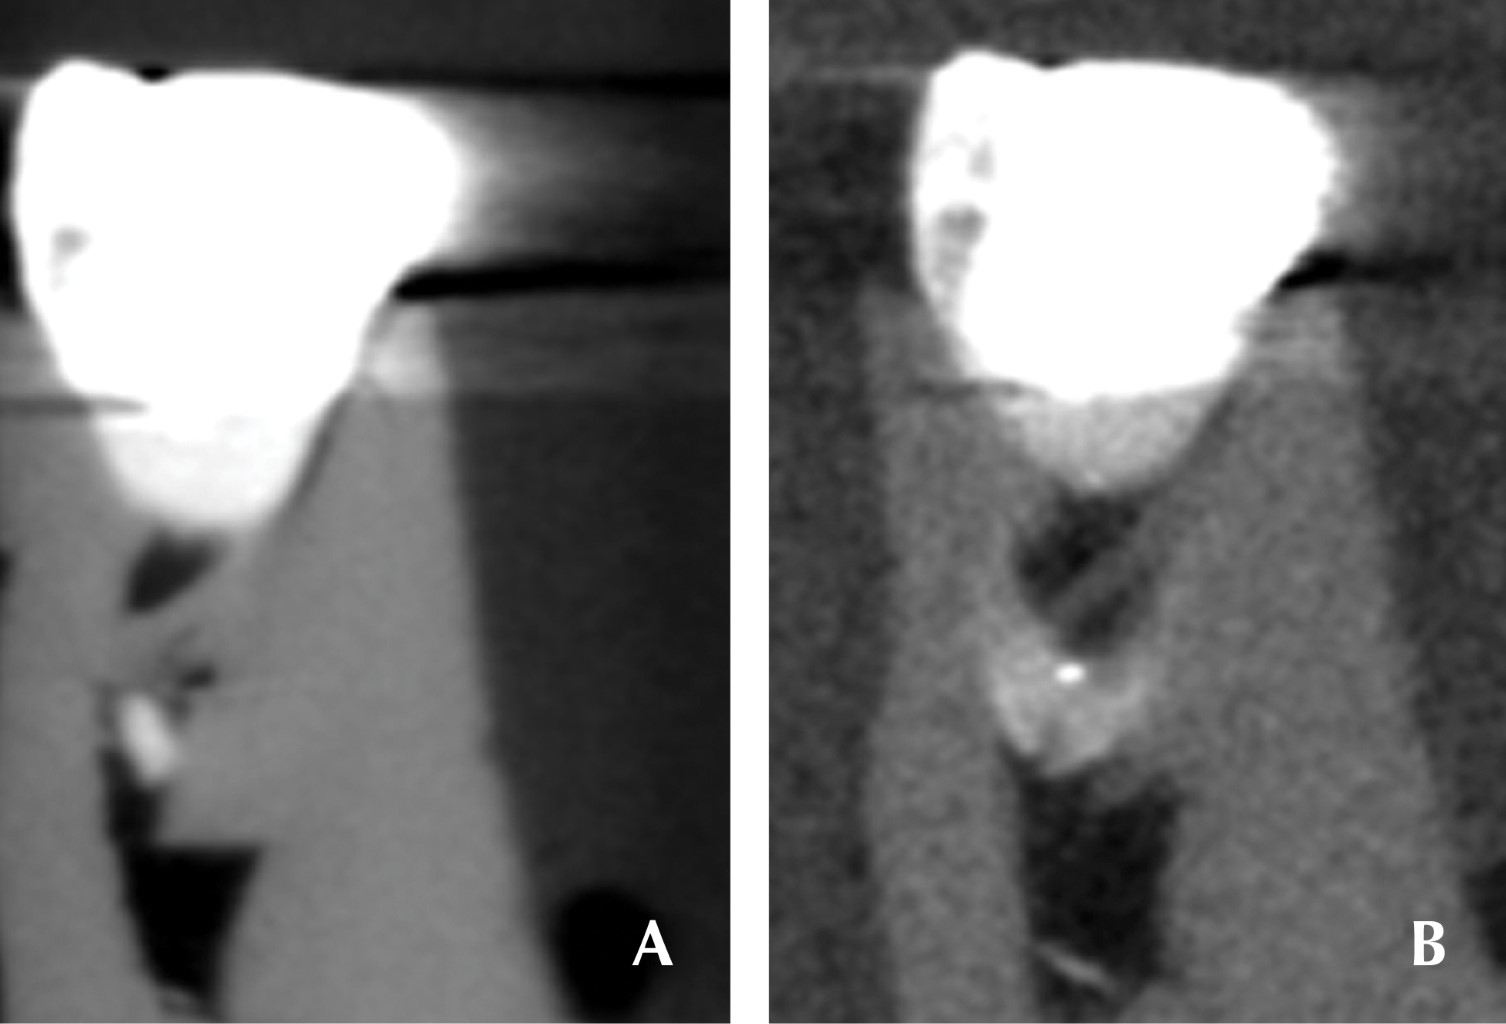

El operador introdujo en un modelo de una pieza dentaria extraída con una restauración metálica ubicada estratégicamente sobre compuesto de modelar de bajo peso atómico por dentro de un tubo plástico con agua en su interior. Se le realizaron exposición en tomográficas en un equipo marca Kodak 9000 con valores de 66 kV, 6.3 mA, 10.8 seg de tiempo de exposición y voxel de 76 µm. Se realizó en la primera toma sin filtro y después con filtros ubicados estratégicamente a la salida del foco radiográfico, a la entrada del sensor y rodeando al diente. Se utilizaron filtros de aluminio de espesor de 1 mm; y otros dos de cobre de 0.5 mm y de 0.1 mm. Una vez obtenido el volumen se procesó el corte axial y se obtuvo una imagen oblicua que abarca la pieza de mesial a distal (Figura 1A). Se realizaron a partir de corte oblicuo tres cortes perpendiculares. El primero exactamente en el medio de la pieza (Figura 1B); otro, a una distancia de 1.2 mm por mesial (Figura 1C) del corte medio y el último a 1.2 mm por distal del corte inicial (Figura 1D). Todos los cortes con el espesor mínimo de 76 µm. A partir de allí se realizaron las mediciones de la extensión del artefacto en ancho y alto en cada corte final (Figura 2) (Tablas 1 y 2).

A posteriori se realizó el mismo procedimiento y metodología con un implante dentario en lugar de la pieza dentaria ubicado sobre compuesto de modelar de bajo peso atómico por dentro de un tubo plástico con agua en su interior (Tabla 3). Se realizaron exactamente la misma toma con los mismos valores y los mismos filtros que en el primer método.